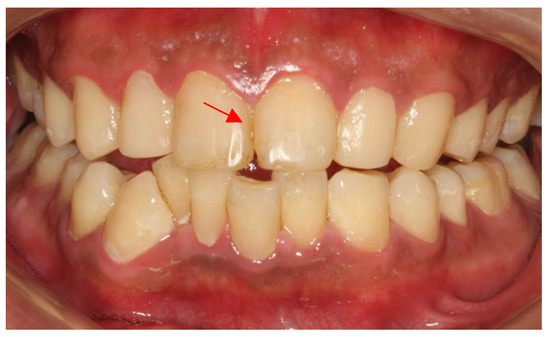

However, after this return visit, the patient was lost to follow-up for 3 years. Three years later (5 years after the first treatment), the patient came back with dental plaque covering the whole tooth surface, severe periodontal inflammation, many secondary caries and the retention, margin fitness and color matching of the restorations were poor (Figure 8a). Retreatment at this time could not achieve a perfect therapeutic effect (Figure 8b) and the reassessment of his caries risk this time was high risk again.

Figure 8.

(a) Five years after treatment; (b) Retreatment completed.

To sum up, using the caries risk assessment, patients received personalized caries management plans. According to the caries treatment difficulty assessment, patients received appropriate referrals and treatments. The effect of the first treatment was satisfied, which was a good foundation for later maintenance. Regular follow-up visits enable dentists to deal with new problems in time. However, this case suggests that the loss of follow-up in just 3 years almost destroyed the dentist’s previous efforts, and even careful retreatment failed to achieve aesthetic restoration. Therefore, regular follow-up and personalized management of high/medium risk groups is necessary for the treatment and maintenance of dental caries.